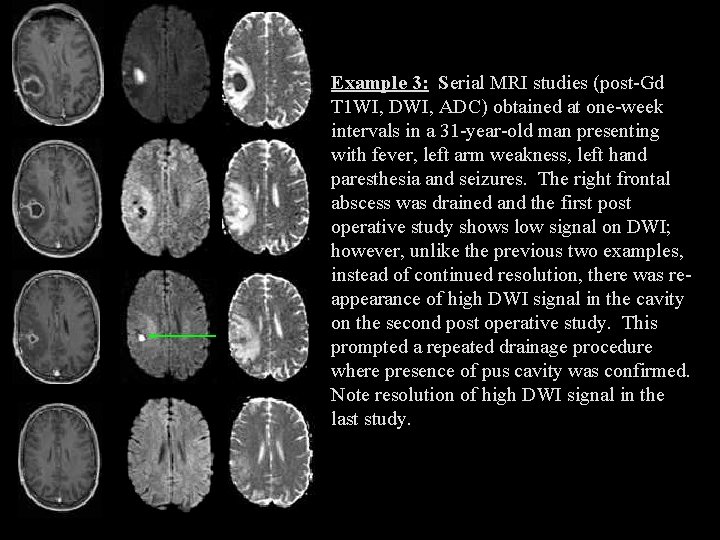

Example 3: Serial MRI studies (post-Gd T 1 WI, DWI, ADC) obtained at one-week intervals in a 31 -year-old man presenting with fever, left arm weakness, left hand paresthesia and seizures. The right frontal abscess was drained and the first post operative study shows low signal on DWI; however, unlike the previous two examples, instead of continued resolution, there was reappearance of high DWI signal in the cavity on the second post operative study. This prompted a repeated drainage procedure where presence of pus cavity was confirmed. Note resolution of high DWI signal in the last study.